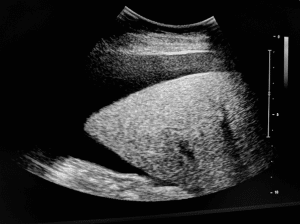

5-Paracentesis Â

Evidence of Ascites accumulation through ultrasonographyÂ

Probe SelectionÂ

Low-Frequency Curved Array Probe:Â

Use: Ideal for abdominal imaging.Â

Frequency Range: 2-5 MHz.Â

Advantages: Provides good depth penetration, essential for visualizing deeper structures and fluid collections.Â

Elements of examination:Â

Static Approach:Â

Technique: The static approach is done using ultrasound where the anticipated region of needle placement is detected and marked before the procedure is done. Abdomen is physically examined with a view of identifying some of the accumulations of fluids, a right location to access the fluid is then identified.Â

Advantages: This method allows to careful plan and ensures that the needle is inserted in most appropriate area, reducing the risk of complications.Â

They help the physician to determine exact depth of the target fluid and thereby increases the chances of penetrating correct target and not the surrounding tissues.Â

Dynamic Approach:Â

Technique: The dynamic approach implies the ultrasound imaging during the paracentesis process when it is being performed. The ultrasound probe remains in contact with the patient’s skin while the needle is inserted; this way the operator gets real time view of the needle path and its neighbouring fluid.Â

Advantages: This approach leads to constant feedback, thus great flexibility in changing the position of the needle if required. It can help avoid injury to nearby organs and vessels and can improve the accuracy of fluid aspiration.Â